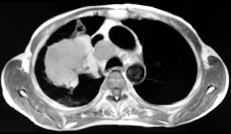

- 单项选择题男,68岁, 右侧胸痛伴右上臂麻木1周,胸部CT、MRI扫描如图, 最可能的诊断为 ( )

A、右上肺硬化性血管瘤

B、右上肺肉瘤并纵隔淋巴转移

C、右上肺不张

D、右上肺中央型肺癌并右上肺不张,纵隔淋巴转移

E、右上肺周围型肺癌并纵隔淋巴转移